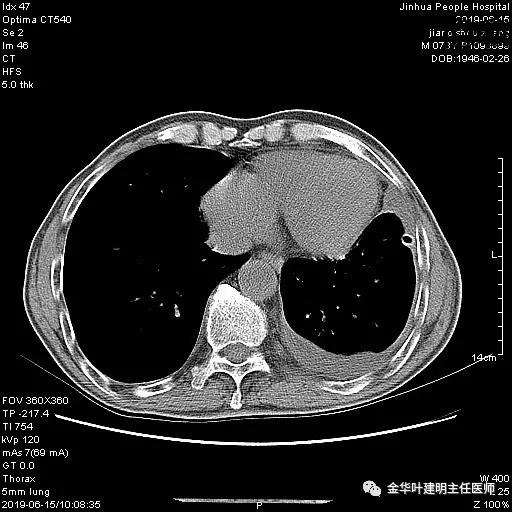

6.15上午:24小时胸管引流出血性液250ml;复查胸部CT示:

以上是肺窗表现,下面为纵隔窗影像: